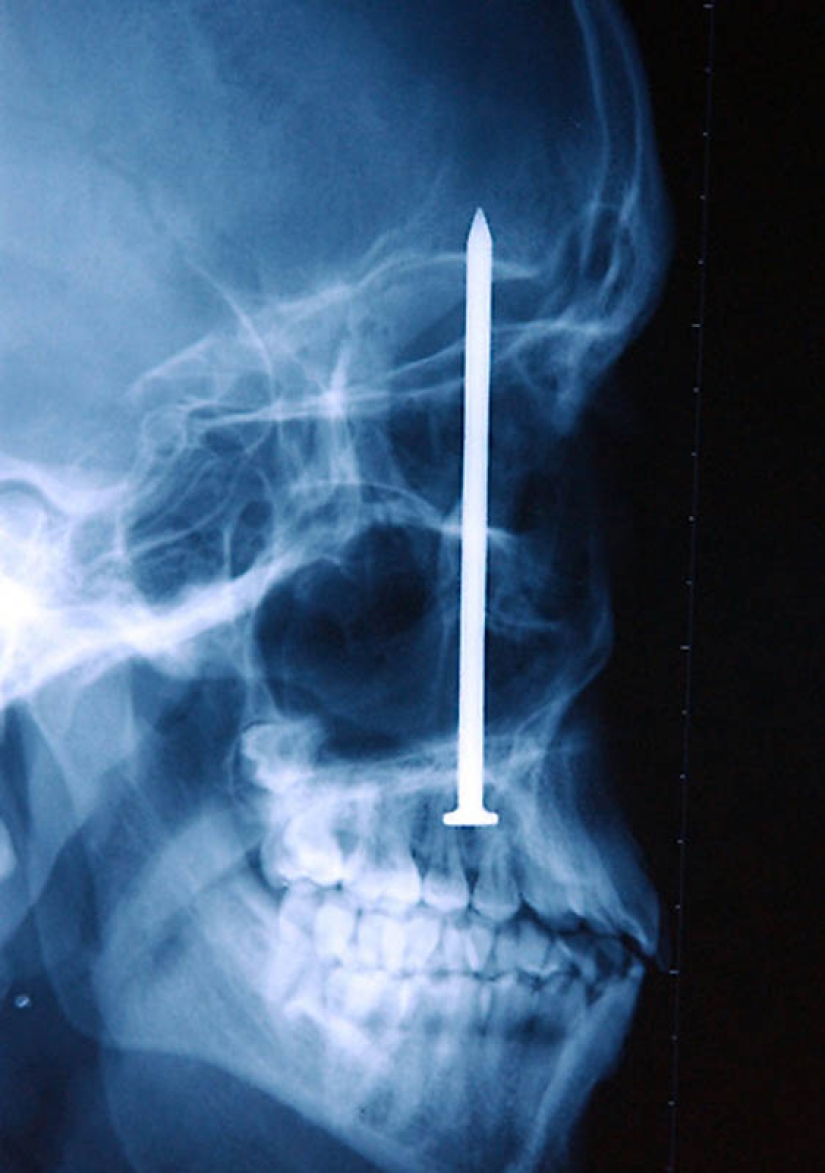

13. Nail in the human skull-the patient accidentally shot himself with a pneumatic hammer. He did not even realize that he had shot himself – a nail 10 cm long was found only after 6 days.